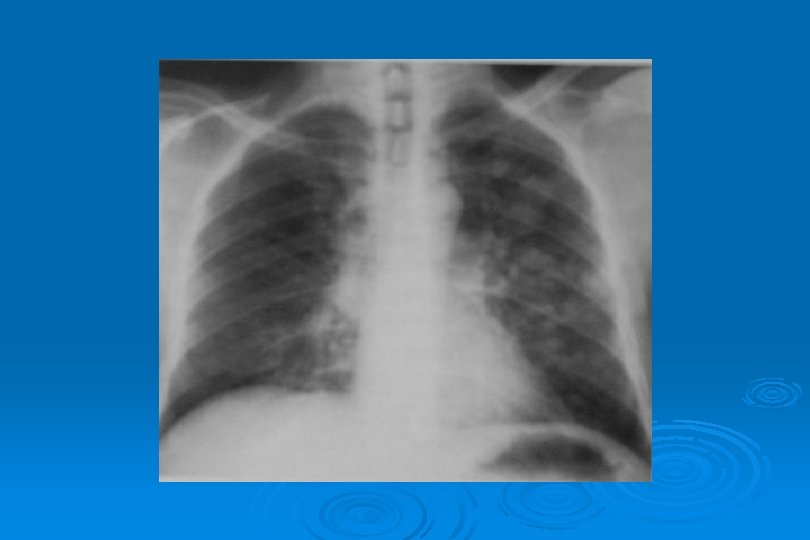

İnfluenza Virüs Pnömonisi

LOKALİZE VEYA YAYGIN HEMORAJİK ÖDEM Lokal olduğunda radyolojik görünümü segmenter veya lober pnömoniye benzer Ø Yaygın hemorajik ödem akut ve şiddetli viral pnömonide hızla ortaya çıkan bir tablodur Ø Perihiller perifere doğru azalan yaygın alveoler opasiteler görülür Ø Bazen plevral effüzyon olaya eşlik eder Ø İnfluenza virüsü en sık nedendir Ø